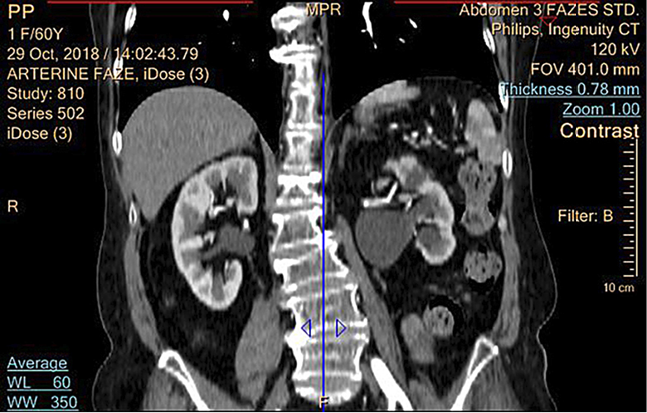

Atlikus KT (2018-10-29) – kairiojo inksto ryški hidronefrozė (iki 34 mm), dešinėje geldelė praplėsta iki 12 mm; abipus šlapimtakiai nepraplėsti (žr. 2 pav.).

2 pav. Pacientės inkstų KT prieš operaciją